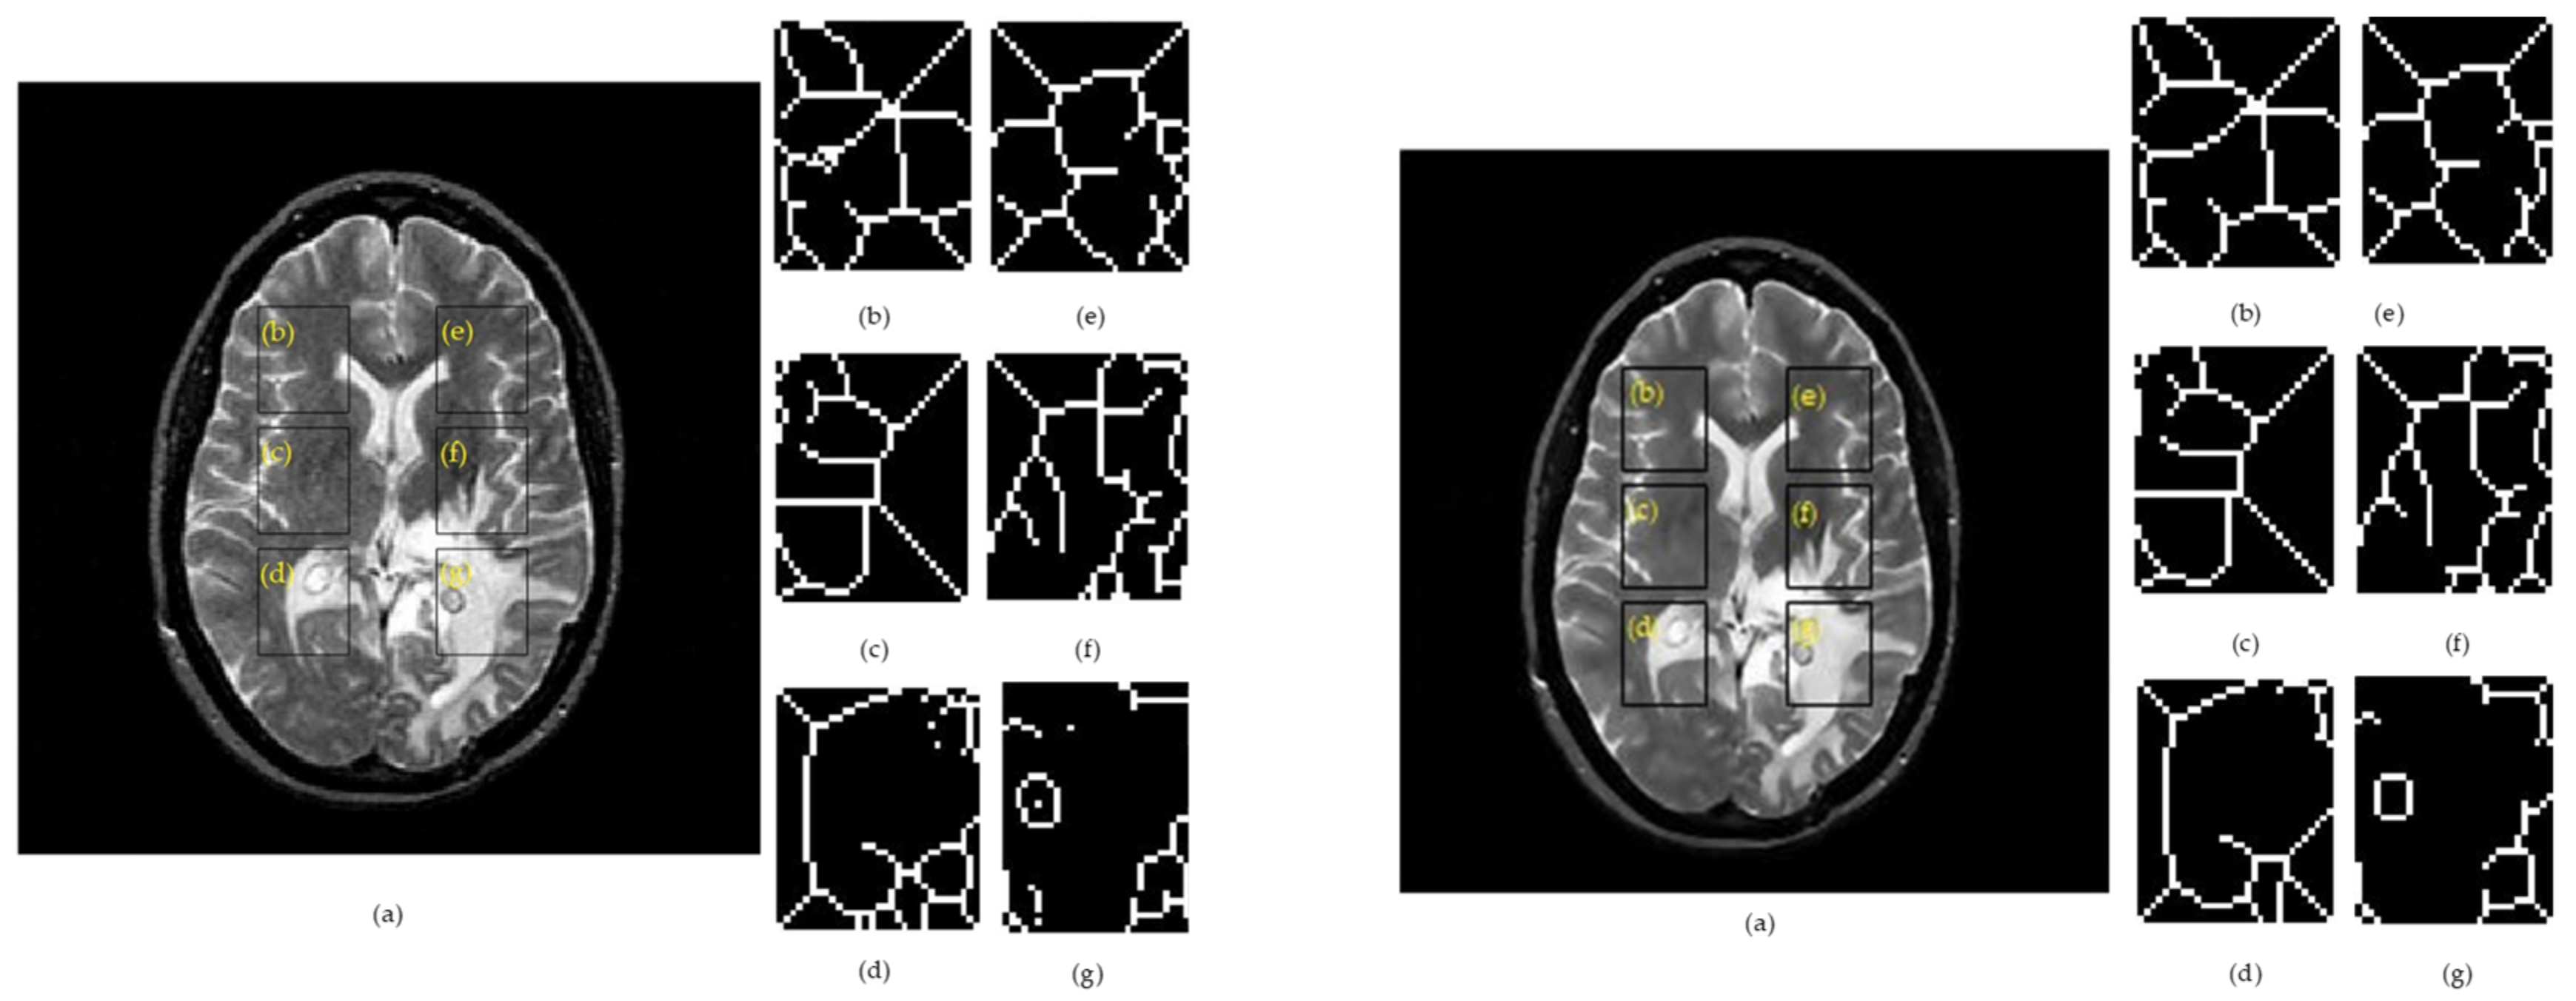

Figure 2 and Figure 3 show examples for the implementation of SSIMs and skeletonization for right– left correspondents for a raw image containing Rician noise (left panel) and a filtered image by the anisotropic diffusion filter (right panel).

Figure 3. Results of the skeleton algorithm for a T2w image belonging to a patient with glioma, where: Left side: (a) raw image. Right side: (a) denoised image. (b) ROI 1L; (c) ROI 2L; (d) ROI 3L; (e) ROI 1R; (f) ROI 2R; and (g) ROI 3R.